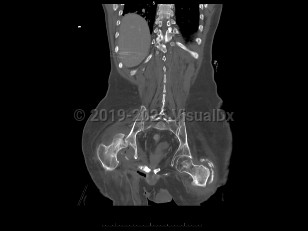

Septic arthritis

An infection of a joint most frequently caused by bacteria (although fungi, parasites, and mycobacteria may also rarely cause this infection).

This infection occurs most commonly as a result of hematogenous seeding of the joint in the setting of bacteremia. A joint may be inadvertently inoculated with a pathogen at the time of surgery or trauma. In some patients, a severe soft tissue infection may spread to involve a nearby joint.

Common pathogens responsible for this infection include Staphylococcus aureus, Streptococcus species, gram-negative bacilli, and Neisseria gonorrhoeae.

Risk factors for this infection include old age, diabetes mellitus, recent joint surgery or procedure, skin infection, the presence of a prosthetic joint, or immunosuppression. Patients with rheumatoid arthritis or who abuse intravenous (IV) drugs are also at increased risk for this infection.

Patients present with a swollen, warm, stiff, and painful joint. Fever may be present. The majority of the time, a single joint (usually the knee) is involved. Symptoms develop over 1-2 weeks. If the infection is caused by N gonorrhoeae, patients classically also present with a rash and tenosynovitis. If the infection is due to fungi or mycobacteria, the symptoms may be subtler and may worsen more gradually.